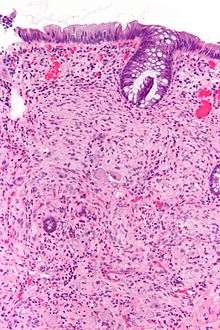

Pathology

Pathologically, ganglioneuromas are composed of ganglion cells, Schwann cells and fibrous tissue.[4] Ganglioneuromas are solid, firm tumours that typically are white when seen with the naked eye.